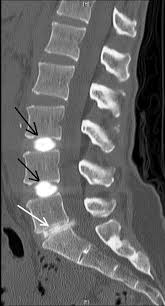

Your doctor will use an imaging technique (fluoroscopy) that enables him or her to watch as the needle enters your body. Fluoroscopy allows more precise and safer placement of the needle into the center of the disk to be examined. A contrast dye is then injected into the disk, and an X-ray or CT scan is taken to see if the dye spreads.

If the dye stays in the center of the disk, the disk is normal. If the dye spreads outside the center of the disk, the disk has undergone some wear-and-tear change. These changes may or may not be the cause of your pain.

Typically, if a disk is causing your back pain, you will feel pain during the injection that's similar to the back pain you have daily. If a disk is normal, there's little pain during injection. During discography, you will be asked to rate your pain.After a Post Discogram